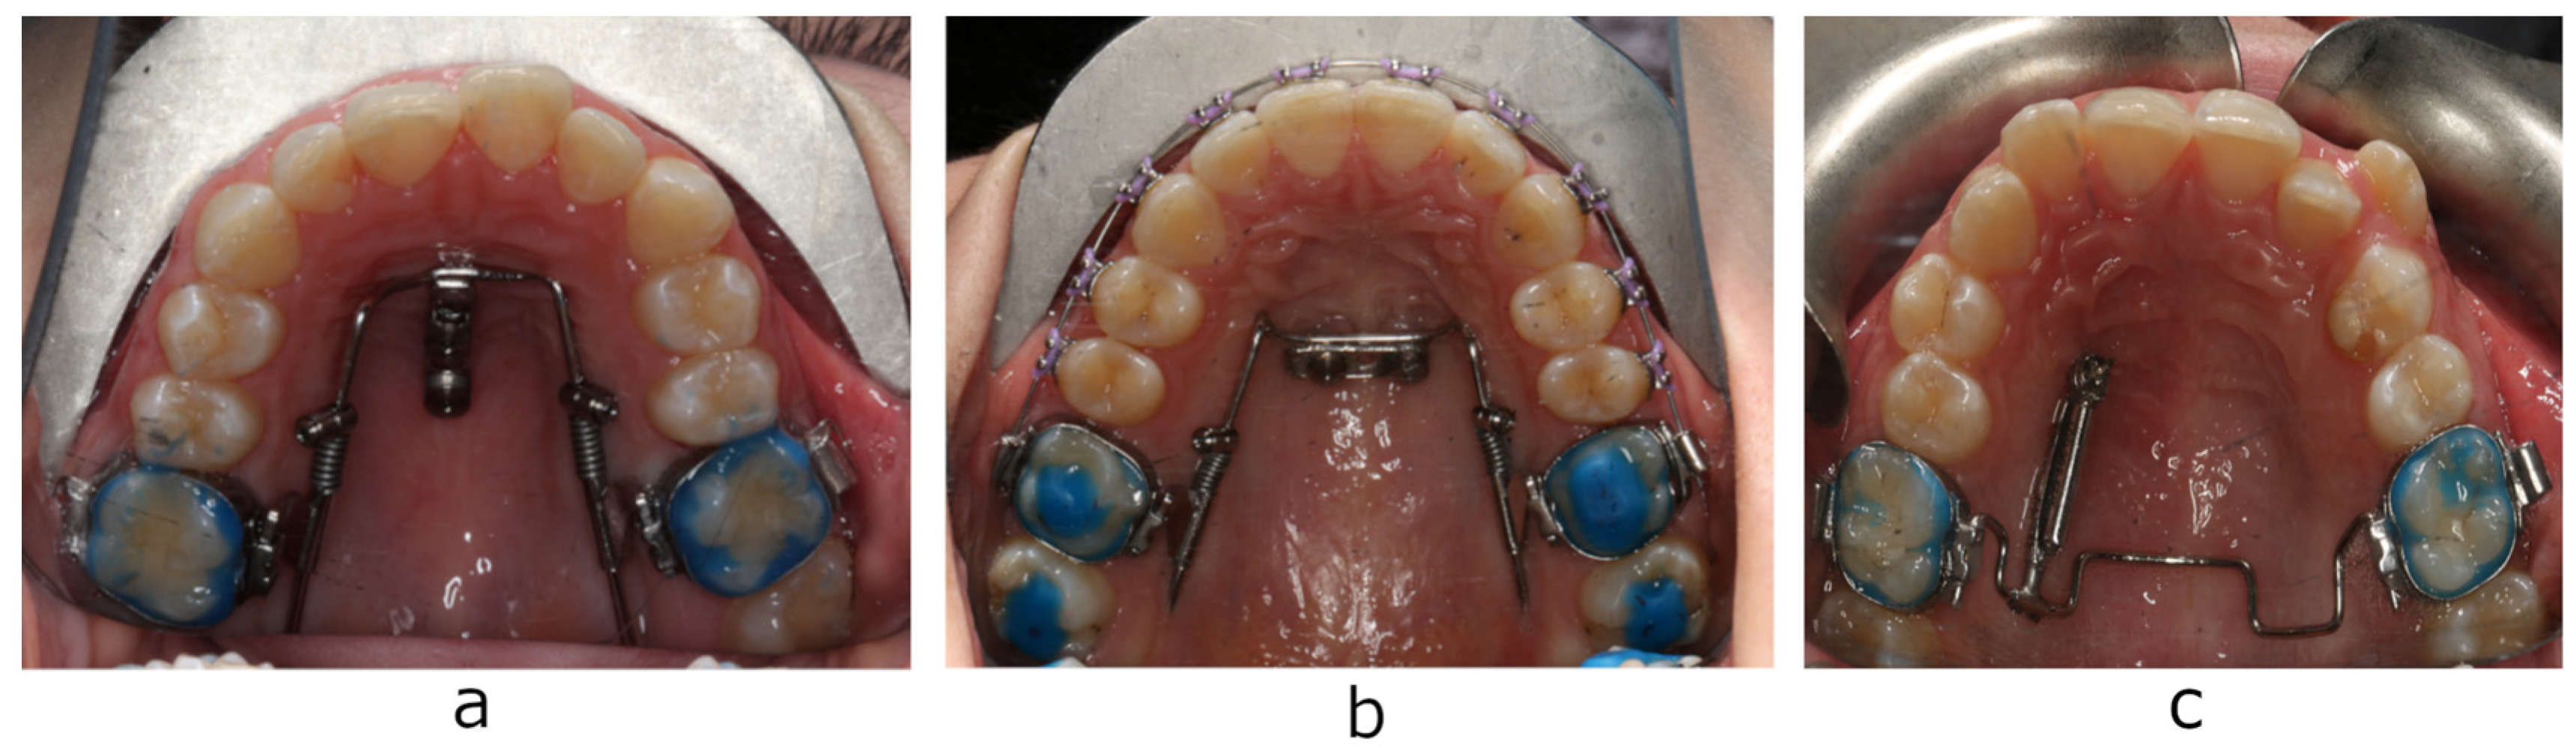

2. Materials and Methods

2.2. Measurements